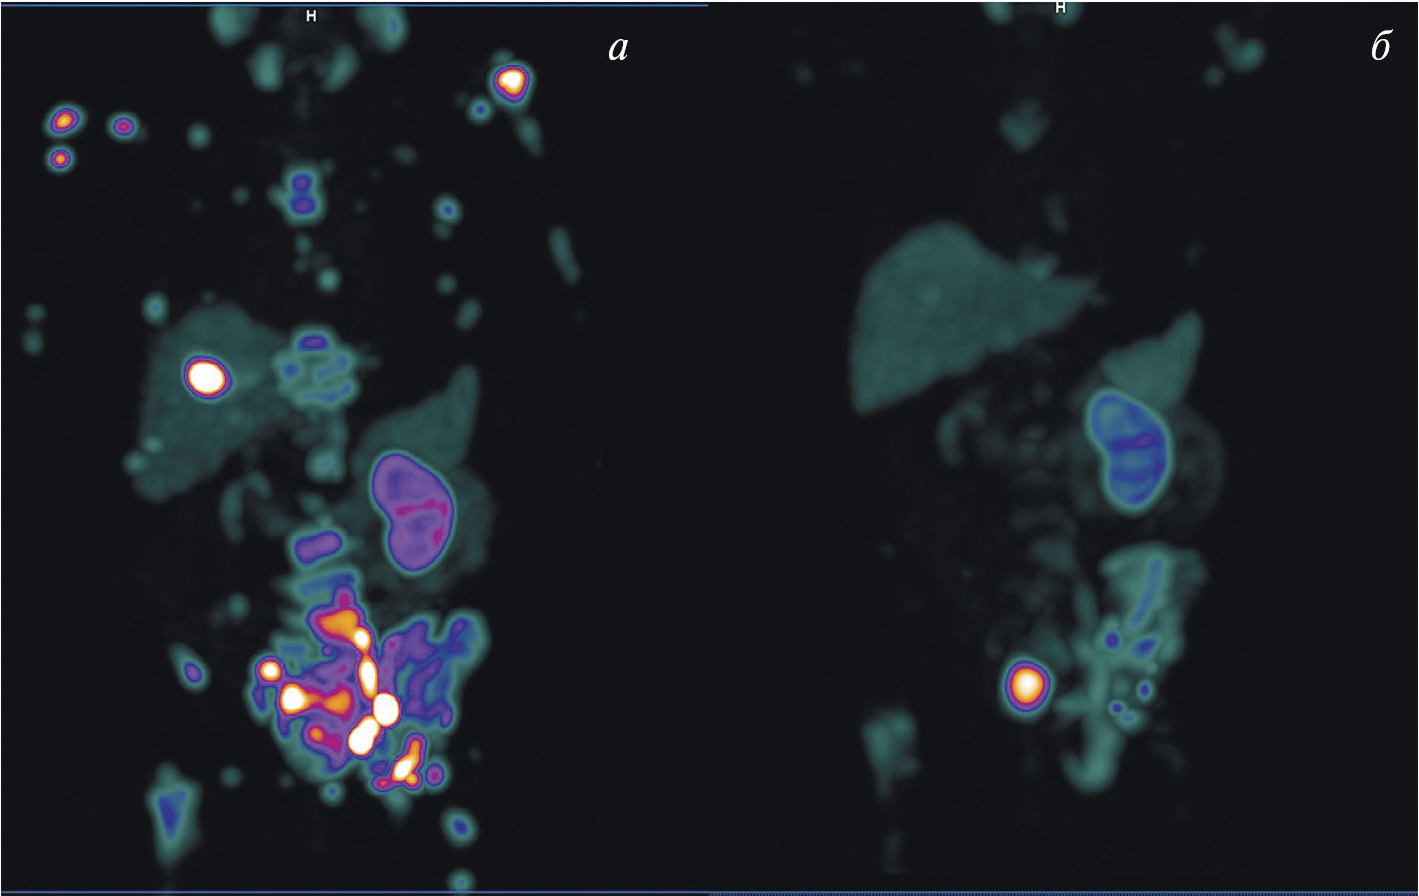

В мировой ядерной медицине для сцинтиграфии обычно применяют 111In-пентетреотид, или 111In-октреотид ([111In-DTPA]octreotide, OctreoScan, Tyco Healthcare, США; АО “Фармсинтез”, Россия). Основные показания к его использованию — стадирование, рестадирование и мониторинг лечения нейроэндокринных SSTR-позитивных опухолей. В последние годы 111In-пентетреотид служит для радионавигации при хирургическом лечении новообразований с гиперэкспрессией соматостатиновых рецепторов. К сожалению, физические характеристики индия-111 (длительный период полураспада, неоптимальный для регистрации на гамма-камере спектр излучения, высокая стоимость циклотронного производства) ограничивают его применение в радионуклидной диагностике. В связи с этим не подвергается сомнению актуальность создания в России меченного технецием-99м октреотида для ОФЭКТ-диагностики нейроэндокринных опухолей. Разработкой такого радиофармпрепарата в рамках проекта федеральной целевой программы “Фарма-2020” занимался ТПУ в сотрудничестве с НИИ онкологии Томского НИМЦ. Клинические испытания отечественного 99mТс-октреотида продемонстрировали его высокую эффективность при диагностике и стадировании НЭО (рис. 3). В настоящее время набор для приготовления этого РФЛП зарегистрирован в России под названием “Нейроскан, 99mТс”, а его производство налажено в ТПУ.

Рис. 3. ОФЭКТ/КТ с 99mТс-октреотидом пациента с нейроэндокринным раком лёгкого: а — конгломерат первичной опухоли и метастазов в лимфатические узлы; б — метастазы в кости; в – селезёнка

Для ПЭТ-диагностики нейроэндокринных опухолей нашли применение аналоги соматостатина, меченные 68Ga. При этом наиболее популярными стали 68Ga-DOTATATE и 68Ga-DOTATOC. Сравнительная оценка диагностической эффективности выявила их практически одинаковую точность, однако уровень аккумуляции 68Ga-DOTATOC в опухоли оказался выше [16]. При гиперэкспрессии SSTR2 и SSTR5 предпочтение следует отдавать 68Ga-DOTANOC, который характеризуется более высокой афинностью к этим рецепторам [17]. Для ПЭТ-диагностики нейроэндокринных опухолей также перспективны 64Cu-DOTATATE [18] и 18F-FP-Gluc-TOCA [19].